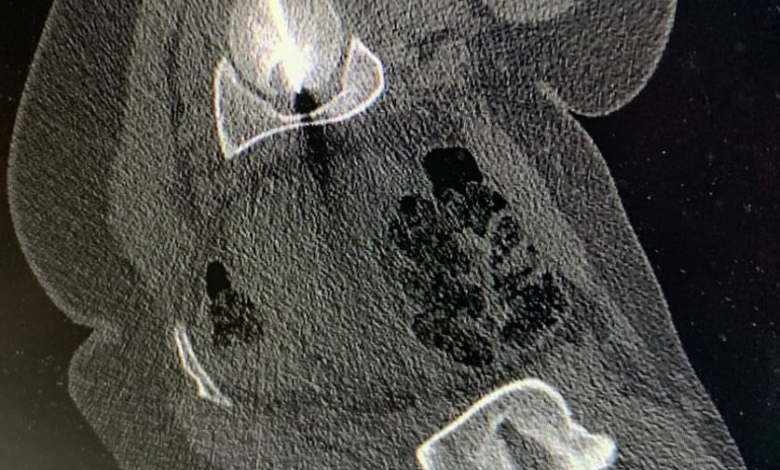

وبيّن البطوش، أنّ الفريق الطبي نجح في الوصول إلى مركز الورم بدقة عالية باستخدام تقنيّة التصوير الطبقيّ المحوريّ (CT Scan)، تلا ذلك إجراء الكي بالتقنيّة الحراريّة باستخدام المايكروويف (Microwave Ablation)، وهي من أحدث التقنيّات العالميّة في علاج أورام العظام دون الحاجة إلى التدخّل الجراحيّ المفتوح.